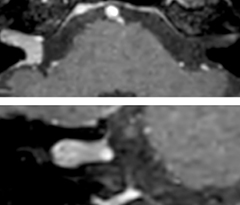

The abbreviated MS protocol for brain is only around 9 minutes, so in case of suspected multiple sclerosis, one or two more advanced sequences may be added, such as PSIR (phase sensitive inversion recovery) or susceptibility-weighted sequences to help us make more confident diagnoses in these inflammatory cases.

In this example, the optional 3D multishot susceptibility weighted sequence with 0.6 mm isotropic voxels is 2 lesions with a central vein sign (arrows) and one lesion with a phase-rim sign (arrowhead). The total scan time, including SmartBrain and axial PD/T2 3mm, is 11:10 min. and is 18:30 min. with the optional 3D PSIR and 3D SWI multishot included.

“We used to have long examination times for certain types of patients, a few lasting more than 40 minutes,” says Dr. Savatovsky. “What is remarkable, is that now all these examinations are below 30 minutes, which opens up opportunity to add more sequences when needed. It’s really hard to keep a patient for more than 40 minutes in the scanner, but because we have now cut scan times by at least 10 minutes, we can add more sequences without making the exam too long. And this is where the new system helps us make a difference. Examples include our examinations for informing brain tumor classification or giant cell arteritis workup, or for intracranial wall imaging – so in patients where we need several advanced sequences or high resolution sequences.” “We added three additional sequences in our brain neoplasm classification exam: a 3D SWI sequence, APT and ASL on top of 3D morphologic sequences, an isotropic DSC (dynamic susceptibility contrast) and multivoxel spectroscopy. I think that in patients that need a classification for brain mass, for example, we can provide a more detailed and confident diagnosis than before, allowing the clinicians to decide for either a medical workup if no tumor is suspected, or for neurosurgery as soon as possible if a neoplasm is suspected.” “In multiple sclerosis patients, we increasingly include a multishot susceptibility sequence [3] in our routine cases, thanks to the shorter scan times. Our abbreviated MS protocol for brain is around 8 to 9 minutes, so we can ask for one or two additional sequences to visualize the central veins, or to get an additional contrast to better depict posterior fossa lesions. In cases of white matter lesions of unknown significance on FLAIR images, for example when we see high signal hyperintensities in the brain, we can add on more advanced sequences such as PSIR (phase sensitive inversion recovery) or susceptibility-weighted sequences to help us in distinguishing between MS and nonspecific or vascular abnormalities in these inflammatory cases.”